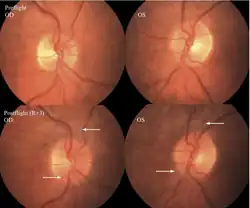

The first U.S. case of visual changes observed on orbit was reported by a long-duration astronaut that noticed a marked decrease in near-visual acuity throughout his mission on board the ISS, but at no time reported headaches, transient visual obscurations, pulsatile tinnitus or diplopia (double vision). His postflight fundus examination (Figure 1) revealed choroidal folds below the optic disc and a single cotton-wool spot in the inferior arcade of the right eye. The acquired choroidal folds gradually improved, but were still present 3 year postflight. The left eye examination was normal. There was no documented evidence of optic-disc edema in either eye. Brain MRI, lumbar puncture, and OCT were not performed preflight or postflight on this astronaut.[5]

The seventh case of visual changes associated with spaceflight is significant in that it was eventually treated postflight. Approximately 2 months into the ISS mission, the astronaut reported a progressive decrease in his near and far acuity in both eyes. The ISS cabin pressure, CO2 and O2 levels were reported to be within normal operating limits and the astronaut was not exposed to any toxic substances. He never experienced losses in subjective best-corrected acuity, color vision or stereopsis. A fundus examination revealed a grade 1 bilateral optic-disc edema and choroidal folds (Figure 15).[5]